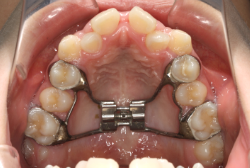

混合歯列期から治療開始した側方拡大による非抜歯症例

「配列の凸凹を治したい」という主訴で来院したケースです。診断の結果、永久歯がすべて生えそろうと、かなり厳しい叢生(歯並びの凸凹のことです)になる可能性が高いと判明しました。原因としては特に上の顎の骨が小さいため、歯を収容する容量不足になっていると診断しました。このケースの場合は、成長発育期に治療開始しますので、顎の骨を土台ごと大きくすることが可能です。

そこで、まず急速拡大装置を使用して上顎骨の拡大を行い、上顎骨の容量が拡大したことを確認後、マルチブラケット装置を使って全体の修正をする、と言う二段階の作戦をとることになりました。

この時期に使う急速拡大装置は、適切な診断に基づいて正しく使用することで確実に骨を大きくすることができます。拡大することで隙間が確保できるので、永久歯の抜歯を避けることができます。

急速拡大装置を1日1回装置の中央にある拡大ネジを、ご自身で回して頂くことで25日間くらいかけて、6mmほど拡大しました。拡大後は、上顎の前歯の隙間が広がっていることがお分かりいただけると思うのですが、土台の骨ごと広がるのでこのような隙間ができます。その後1年半くらいマルチブラケット装置を使用して、全体の修正を行いました。

結局、歯の本数を減らすことなく、すべてご自分の歯を残して正しい配列にすることができました。このケースの場合、2009年10月より拡大と経過観察を行い、2012年3月より1年2ヶ月マルチブラケット装置を装着、2013年5月に治療を終了しました。2段階で行う治療としては短期間で終了しているケースと思います。